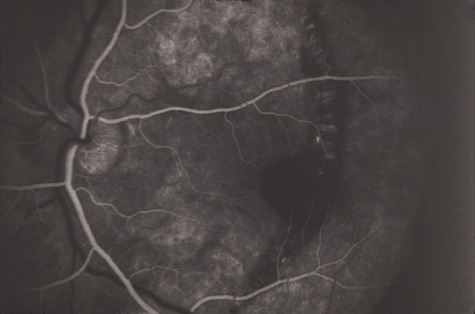

Commotio retinae (Latin, meaning retinal contusion) is a contrecoup injury. It can occur peripherally (Fig. 8) or centrally, in which case it is called Berlin's edema (Fig. 9). Immediately and for several hours after the trauma, the retina appears normal, although the patient may complain of decreased vision. Thereafter, the outer layers of affected retina become opaque. On fluorescein angiography, the opaque retina blocks background choroidal fluorescence, and in most cases there is no leakage into or under the retina (Fig. 10). For years, clinicians had difficulty explaining this blockage, because leakage is expected in conditions with edema. It was then shown in experimental animals and in human autopsy eyes that Berlin's edema is not true edema. The retinal opaqueness is the result of intracellular edema and fragmentation of the photoreceptor outer segments and intracellular edema of the underlying pigment epithelium. There is little or no intercellular fluid.66–69

Fig. 10. A: Commotio retinae in the macula. B: On the angiogram there is no leakage in the area of commotio retinae.